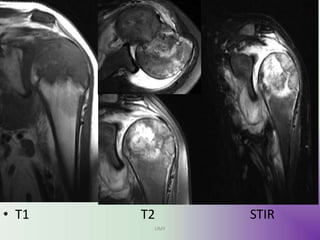

• MRI

• Ideal for the evaluation of transphyseal or

transcortical extension.

• Demonstrating associated surrounding bone

marrow oedema.

•These lesions have signal typical of cartilage: T1

- lesion itself is of low to intermediate signal T2

/ STIR - lesion is of intermediate to high signal

• Fluid-fluid levels may occasionally be seen .

image

• T1 T2 STIR